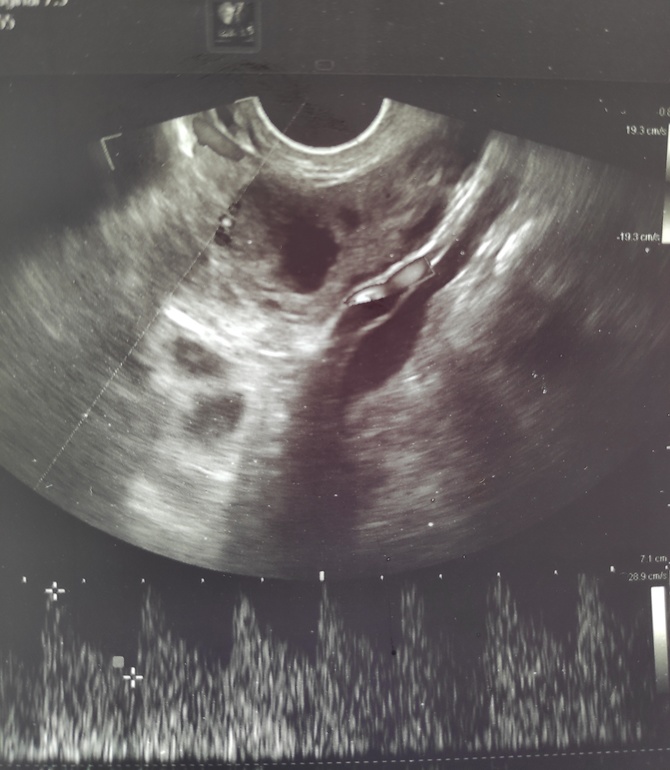

Девочки, на 13 дц укол ХГЧ, на 16 ДЦ врач сказал овуляции не было, лютенизация фолликула... Сегодня 18 ДЦ, врач говорит что овуляция была. Я что должна думать? 😥 Фото сегодняшнего УЗИ прилагается

Потому что по последнему узи указывает все именно на то, что овуляция была.

У вас же здесь ЖТ, а никакой не фолликул!